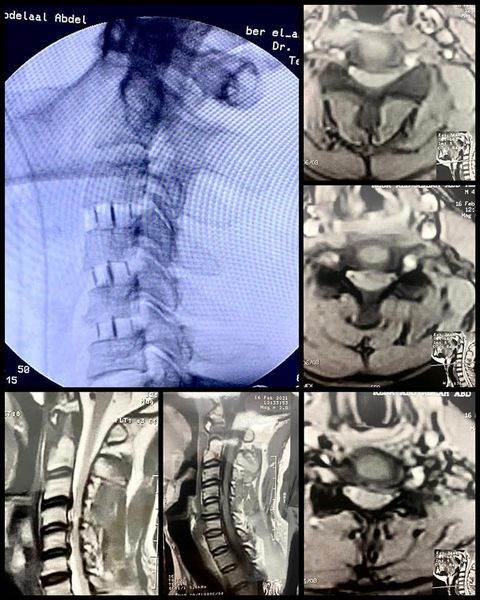

نجح الطاقم الطبي من أساتذة كليات الطب بالجامعات وفريق طبي من مستشفى بئر العبد المركزى فى اجراء عملية جراحية عاجلة وخطيرة لمريض كان يعانى من آلام بالرقبة مع خذلان شديد وضعف بالأطراف الأربعة نتيجة ضيق بالقناة العصبية العنقية وكدمة بالنخاع الشوكى ، وقد خرج المريض من المستشفى مع تحسن ملحوظ فى الحركة والخذلان .

وأعلن الدكتور تامر حمدى مدير إدارة المستشفى ( فى بيان ) أن الفريق الطبي قام بمجرد وصول المريض الى المستشفى باجراء جراحة عاجلة .. حيث تم استئصال ثلاثة غضاريف عنقية أمامية .. مع تركيب أقفاص كربونية للمريض البالغ من العمر ٤١ عاما ، وقد تحسنت حالته وأصبح قادرا على الحركة وتوقف الخذلان .. مشيرا الى أن جراحات الفقرات العنقية هى الأولى من نوعها بمستشفى بئر العبد المركزى ، وهى من أدق جراحات المخ والأعصاب والعمود الفقرى على الاطلاق.